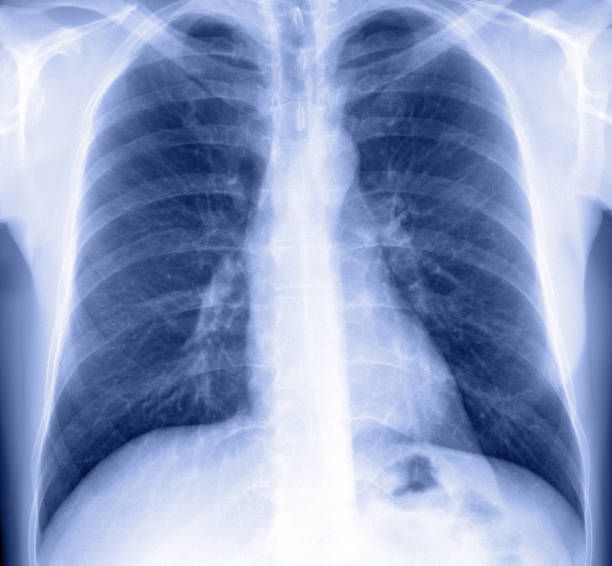

Les personnes présentant un handicap moteur important sont très vulnérables sur le plan respiratoire : l’immobilité, la faiblesse musculaire, les déformations neuro-orthopédiques (la scoliose en particulier) sont autant de facteurs qui peuvent limiter le développement de la cage thoracique et induire un syndrome restrictif.

Par ailleurs, les troubles de la déglutition, le reflux gastro-œsophagien peuvent être responsables d’inhalations à l’origine de lésions parenchymateuses pulmonaires. L’atteinte neurologique centrale peut également avoir un retentissement sur la fonction respiratoire et en particulier en phase de sommeil.

L’atteinte respiratoire varie en fonction de la gravité et du type du handicap. Le positionnement, les traitements orthopédiques (corset siège, corset…) ont également un impact sur la fonction respiratoire dont il faudra tenir compte dans la réflexion de prise en charge des complications neuro-orthopédiques dans cette population.

Il existe un impact fort de l’atteinte respiratoire en termes de qualité de vie et d’espérance de vie.